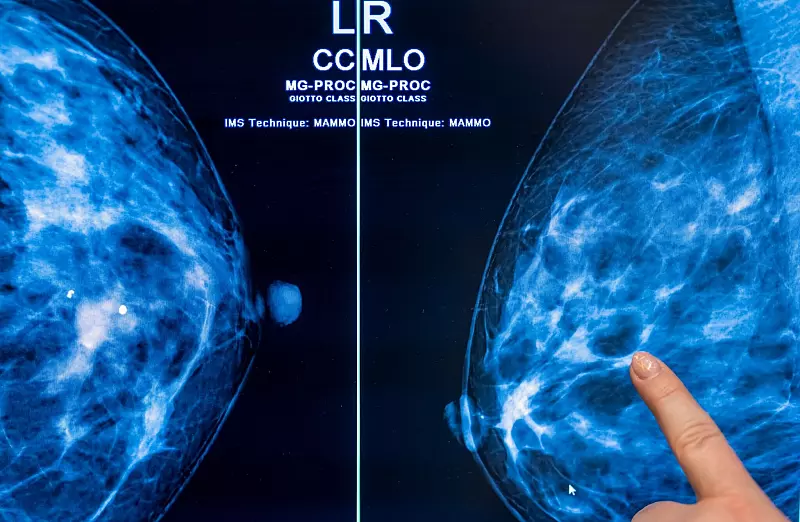

Mit einer Mammografie lassen sich Tumore oft finden, bevor sie sich ertasten lassen – und je früher ein Karzinom erkannt wird, desto besser sind die Heilungschancen. Fortgeschrittener Brustkrebs, bei dem es bereits Metastasen gibt, sei nach wie vor in der Regel nicht heilbar, erklärte Klaus Kraywinkel, Leiter des Zentrums für Krebsregisterdaten am Robert Koch-Institut (RKI).

Im Zuge des Programms können Frauen im Alter von 50 bis 75 Jahren alle zwei Jahre eine Röntgen-Untersuchung der Brust zur Früherkennung in Anspruch nehmen. Bundesweit gibt es laut BfS 95 zertifizierte Screening-Zentren. Frauen, bei denen Symptome bestehen oder ein Verdacht auf Brustkrebs vorliegt, erhalten Mammografien zudem im Rahmen der allgemeinen Versorgung. Der Effekt dieser Untersuchungen wurde in der Studie nicht untersucht.

Christiane Kuhl, Direktorin der Klinik für Diagnostische und Interventionelle Radiologie der RWTH Aachen, betont, mit vorhandenen diagnostischen Möglichkeiten könnte man weit mehr als die 20 bis 30 Prozent Sterblichkeitsminderung erreichen. Ein Problem sei die mangelnde Eignung der Mammografie bei sehr dichtem Brustgewebe. Aktuell würden 20 bis 30 von 100 Frauen mit Brustkrebs nach dem Screening als gesund nach Hause geschickt. Der Tumor falle dann oft erst bei einer Tastuntersuchung als sogenanntes Intervallkarzinom auf – oder erst bei späteren Mammografien.